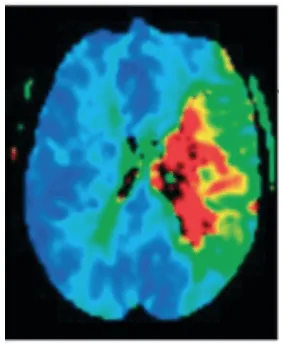

Методы нейровизуализации, такие как магнитно-резонансная томография головного мозга, позволяют подтвердить и локализовать топографию поражения, что крайне полезно при ведении патологии. В острой фазе с помощью диффузионных последовательностей можно определить инфарктную ткань, а также количественно оценить распространённость поражения с помощью перфузионных последовательностей (Ustrell-Roig y Serena Leal, 2007).

Положительное расхождение между объёмом инфаркта и объёмом пенумбры (mismatch) используется как предиктор хорошего ответа на лечение (положительный mismatch указывает на то, что пенумбра значительно превышает инфарктную область, что подсказывает наличие ещё спасаемой ткани головного мозга). Поэтому чрезвычайно важно иметь методы нейровизуализации, которые позволяют разграничить ядро инфаркта и зону пенумбры для прогнозирования исхода пациента и при принятии терапевтических решений для отбора пациентов, которые могут выиграть от реперфузионных вмешательств за пределами традиционных временных окон (García et al., 2022) (figura 1).